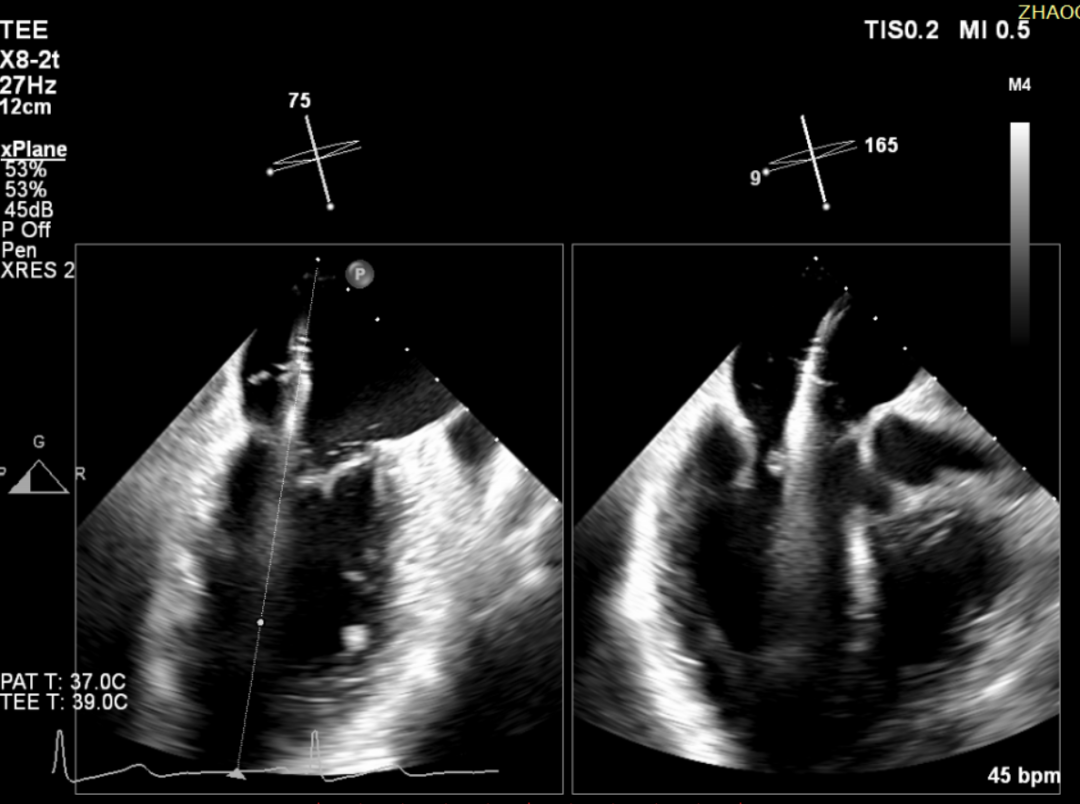

术前TEE+发泡试验证实PFO存在并分级

导丝经下腔静脉顺序进入右房、穿过PFO、进入左房

鞘管及输送封堵器系统跨过PFO进入左房,封堵伞左房面打开

封堵伞右房面打开,回拉,锁定封堵伞,测试封堵器稳定

完全释放封堵器,超声复查位置显示良好、稳定,手术顺利结束